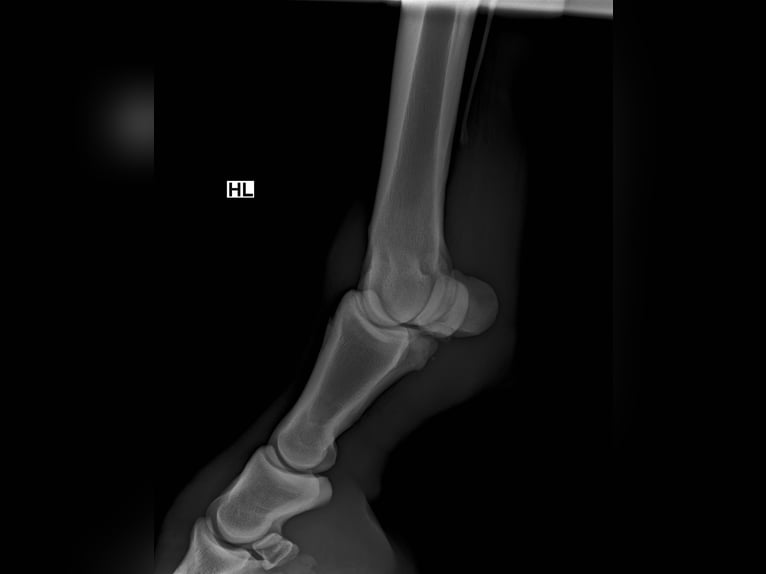

keuringsrapport aanwezig